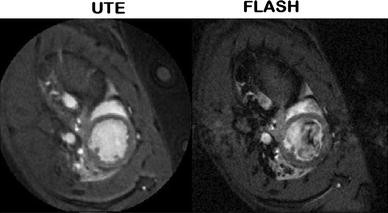

We introduce a fast protocol for ultra-short echo time (UTE) Cine magnetic resonance imaging (MRI) of the beating murine heart. The sequence involves a self-gated UTE with golden-angle radial acquisition and compressed sensing reconstruction. The self-gated acquisition is performed asynchronously with the heartbeat, resulting in a randomly undersampled kt-space that facilitates compressed sensing reconstruction. The sequence was tested in 4 healthy rats and 4 rats with chronic myocardial infarction, approximately 2 months after surgery. As a control, a non-accelerated self-gated multi-slice FLASH sequence with an echo time (TE) of 2.76 ms, 4.5 signal averages, a matrix of 192 × 192, and an acquisition time of 2 min 34 s per slice was used to obtain Cine MRI with 15 frames per heartbeat. Non-accelerated UTE MRI was performed with TE = 0.29 ms, a reconstruction matrix of 192 × 192, and an acquisition time of 3 min 47 s per slice for 3.5 averages. Accelerated imaging with 2×, 4× and 5× undersampled kt-space data was performed with 1 min, 30 and 15 s acquisitions, respectively. UTE Cine images up to 5× undersampled kt-space data could be successfully reconstructed using a compressed sensing algorithm. In contrast to the FLASH Cine images, flow artifacts in the UTE images were nearly absent due to the short echo time, simplifying segmentation of the left ventricular (LV) lumen. LV functional parameters derived from the control and the accelerated Cine movies were statistically identical.